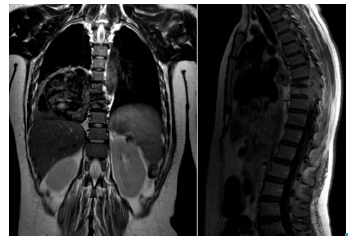

A magnetic resonance (MRI) of the dorsal spine was requested (Figure 2), revealing a right paravertebral mass of 9.9x10x9.4 cm that caused an osteolytic lesion in the vertebral body and lateral antlers of T8 and T9 topography, infiltrating through an intervertebral foramen into the medullary canal, and expansive lytic lesion in the topography of the posterior region of the ninth costal arch diaphysis.

MRI of the dorsal spine, T2-weighted coronal plane and T1-weighted sagittal plane.

Figure 2: MRI of the dorsal spine, T2-weighted coronal plane and T1-weighted sagittal plane.

Source: Document obtained during the study.